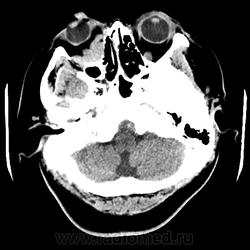

Женщина 48 лет, поступила с подозрением не ОНМК. На КТ -данных за ОНМК не обнаружено, но в правой орбите ретробульбарно мягкотканное образование +45HU, признаков деструкции и ремоделирования костных структур орбиты не наблюдается, медиальная и нижняя прямая мышца отчетливо не дифференцируются, зрительный нерв тесно прилежит к данному образованию. После КУ гомогенное накопление КВ и повышение плотности до +65HU. Экзофтальм. Жалобы на снижение зрения. Год назад делала МРТ ГМ, на снимке патологии орбит не увидел. Идиопатическая псевдоопухоль орбиты?

В мягких тканях носогубного треугольника справа тоже образование.

Контраст